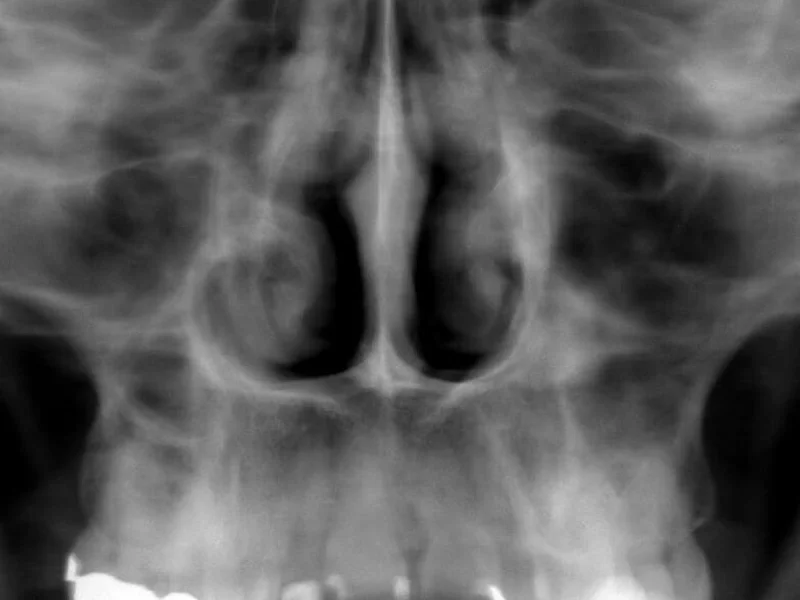

Snimanje digitalnih ortopana, pojedinačnih zuba, sinusa i temporomandibularnog zgloba u Vukovaru.

- –Snimka sinusa

Snimka sinusa

30 € po jedinici